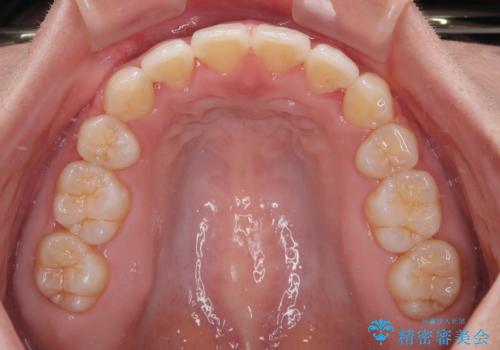

- 全体的なデコボコと口元の突出感を改善したいとのことで来院された患者様です。

このままデコボコを整えるとさらに突出感が増すため、上下左右の第一小臼歯を抜歯し、ワイヤー装置にて矯正しました。

結婚式で途中装置を外した時期がありましたが、2年で治療を終えることができました。